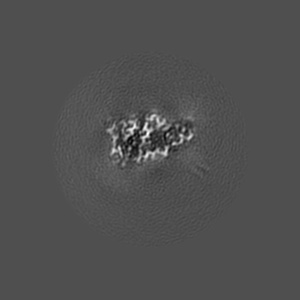

Structure of pathological TDP-43 filaments from ALS with FTLD

Sample: Pathological TDP-43 filaments extracted from the frontal cortex of an individual that succumbed to ALS with FTLD.

Structure of pathological TDP-43 filaments from ALS with FTLD.

Arseni D , Hasegawa M , Murzin AG, Kametani F , Arai M , Yoshida M, Ryskeldi-Falcon B

(2022) Nature , 601 , 139 - 143